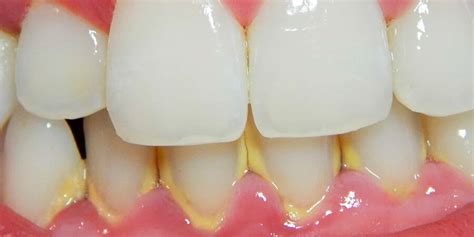

Cuando se cae un trozo de sarro dental, suele indicar acumulación crónica de placa calcificada. Aunque puede parecer un alivio, su caída puede dejar expuesta la encía o una caries. Entendamos qué es el sarro: es esa placa bacteriana que, por falta de higiene adecuada, se endurece y calcifica sobre los dientes (también llamado tártaro dental o cálculo dental). Suele tener un color amarillento o marrón y una textura rugosa. El sarro se adhiere fuertemente al esmalte y no se desprende fácilmente por sí solo con el cepillado normal.

- Retracción de encías: Si hay enfermedad en las encías (gingivitis o periodontitis), las encías pueden haberse retraído o separado del diente. En casos avanzados, el sarro puede estar ocupando ese espacio. Si la encía se retrae lo suficiente, el sarro puede aflojarse.

- Gingivitis: encías rojas, hinchadas y sangrantes.